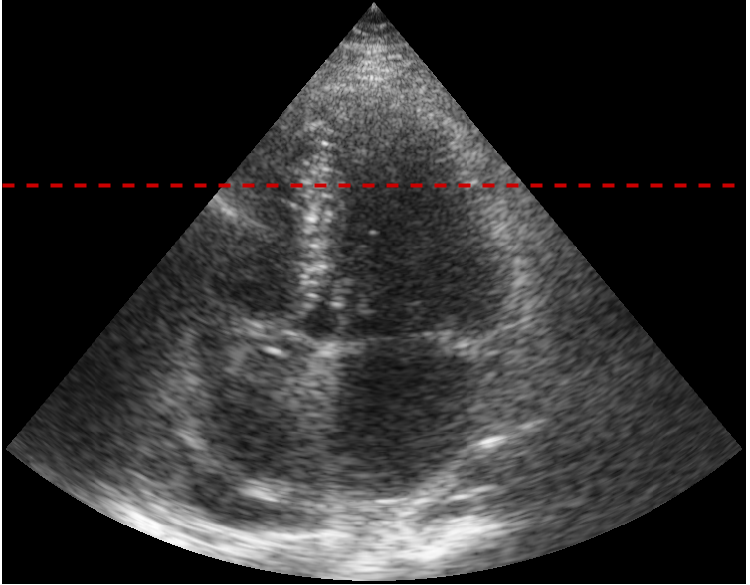

Refer to caption

(a) Plane of the cut for figures b) through e)

(b) Echocardiography

(c) Ground truth segmentation

(d) U-Net prediction

(e) U-Net after temp. reg.

Figure 7: Impact of temporal regularization on a patient with rapid inward/outward radial motion near the apex during early diastole. Each image shows the same radial cut of the image across the whole sequence (a), with figures c), d) and e) overlaying different segmentations on top of the echocardiographic image (b). Figure b) marks where the rapid movement occurs. The motion was captured in the U-Net prediction (d), but was lost in both the smooth ground truth (c) and the temporal regularization of the U-Net (e).